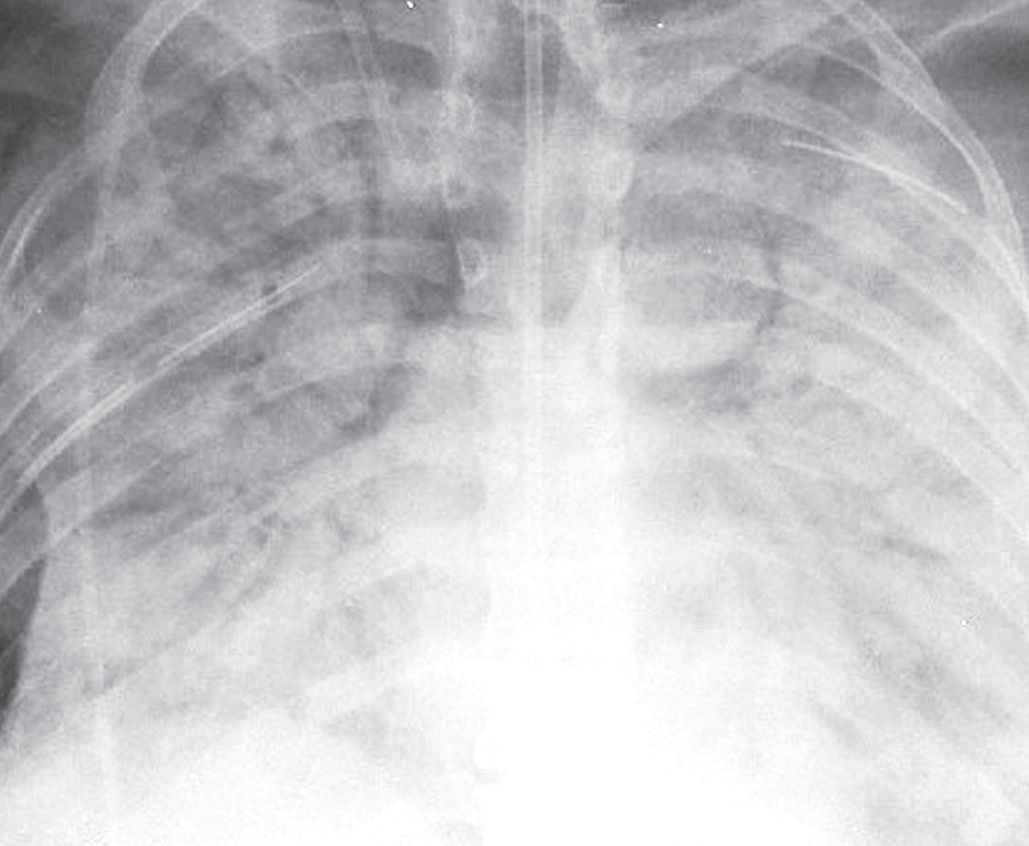

肺的均匀致密影是肺泡内气体完全被代替的结果。实变的肺内血管是不可见的(图2-1A)。

肺实变的患者中,充气的支气管在平片或CT上都能看到,在不透光的肺实质衬托下显示为透光区(图2-1)。这一征象称为空气支气管征。

图2-1 实变:均匀致密影,纹理遮盖,空气 支气管征和CT 血管造影征

A.肺水肿所致的右肺实变。可见双侧实变肺内空气支气管征,肺血管模糊;B. 右肺中下叶肺炎患者增强CT 显示病变区均匀实变,肺体积保持不变,空气支气管征( 黑色箭头) 和致密血管影( 白色箭头),其密度高于邻近实变肺组织( 即“CT血管造影”征)